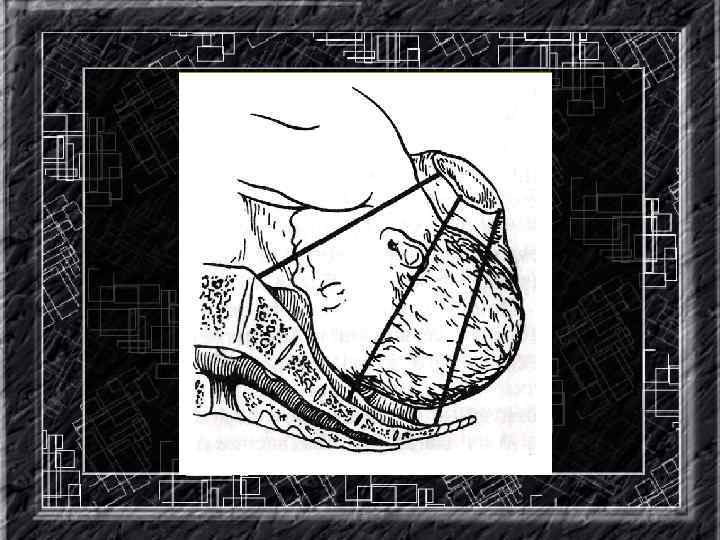

Названия слайдов: • • • • • Слайд 93. КТГ: признаки компрессии пуповины. Слайд 94. КТГ: атипические вариабельные децелерации. Слайд 95. КТГ: атипические вариабельные децелерации. Слайд 96. КТГ: атипические вариабельные децелерации. Слайд 97. КТГ: атипические вариабельные децелерации. Слайд 98. КТГ: поздние децелерации, переходящие в длительную брадикардию. Слайд 99. Первый прием наружного акушерского исследования. Слайд 100. Второй прием наружного акушерского исследования. Слайд 101. Третий прием наружного акушерского исследования. Слайд 102. Четвертый прием наружного акушерского исследования. Слайд 103. Определение диагональной конъюгаты. Слайд 104. Различные варианты расположения стреловидного шва. Слайд 105. Головка прижата к плооскости входа в малый таз. Слайд 106. Головка малым сегментом в плоскости входа в малый таз. Слайд 107. Головка большим сегментом в плоскости входа в малый таз. Слайд 108. Головка в полости малого таза. Слайд 109. Головка в плоскости выхода малого таза.